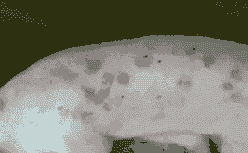

由圆环病毒引起的多发生于12~14周龄仔猪的传染病,以皮肤出现红色丘疹为主,伴有厌食、呆滞、苍白、发热、结膜炎、呼吸困难、腹泻、消瘦等症状。

一种免疫抑制性的皮肤性疾病,在夏季非常多见,表现为猪只体表的不同部位出现数量不等、大小不一的粉红色或红紫色斑点。